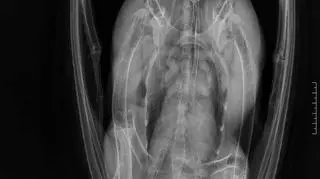

Śrut utkwił w kości ramieniowej ptaka

Postrzelony bocian trafił do lecznicy w czwartek. – Śrut utkwił w kości skrzydła ptaka. Już go wyjęliśmy, ale teraz konieczna jest rehabilitacja – tłumaczy Jakub Kotowicz, wiceprezes ośrodka. Dlatego Edzio, bo takie imię otrzymał bocian, musi przezimować w Przemyślu.